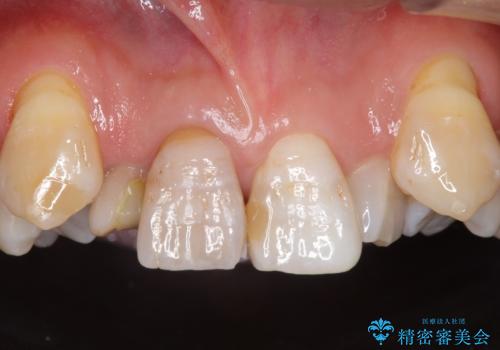

インビザライン矯正 神経のない歯をとって、全て天然歯に